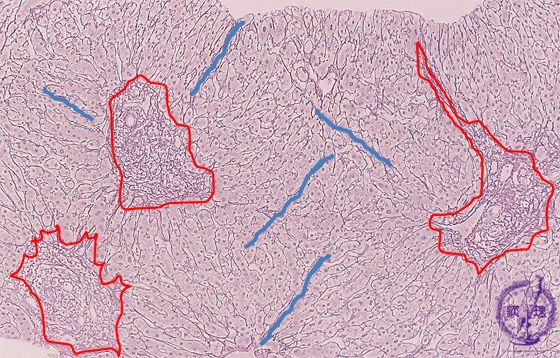

Microscopic image (silver stain, intermediate-power): There is portal fibrous expansion (red box) with varying degrees of bridging fibrosis (blue line).